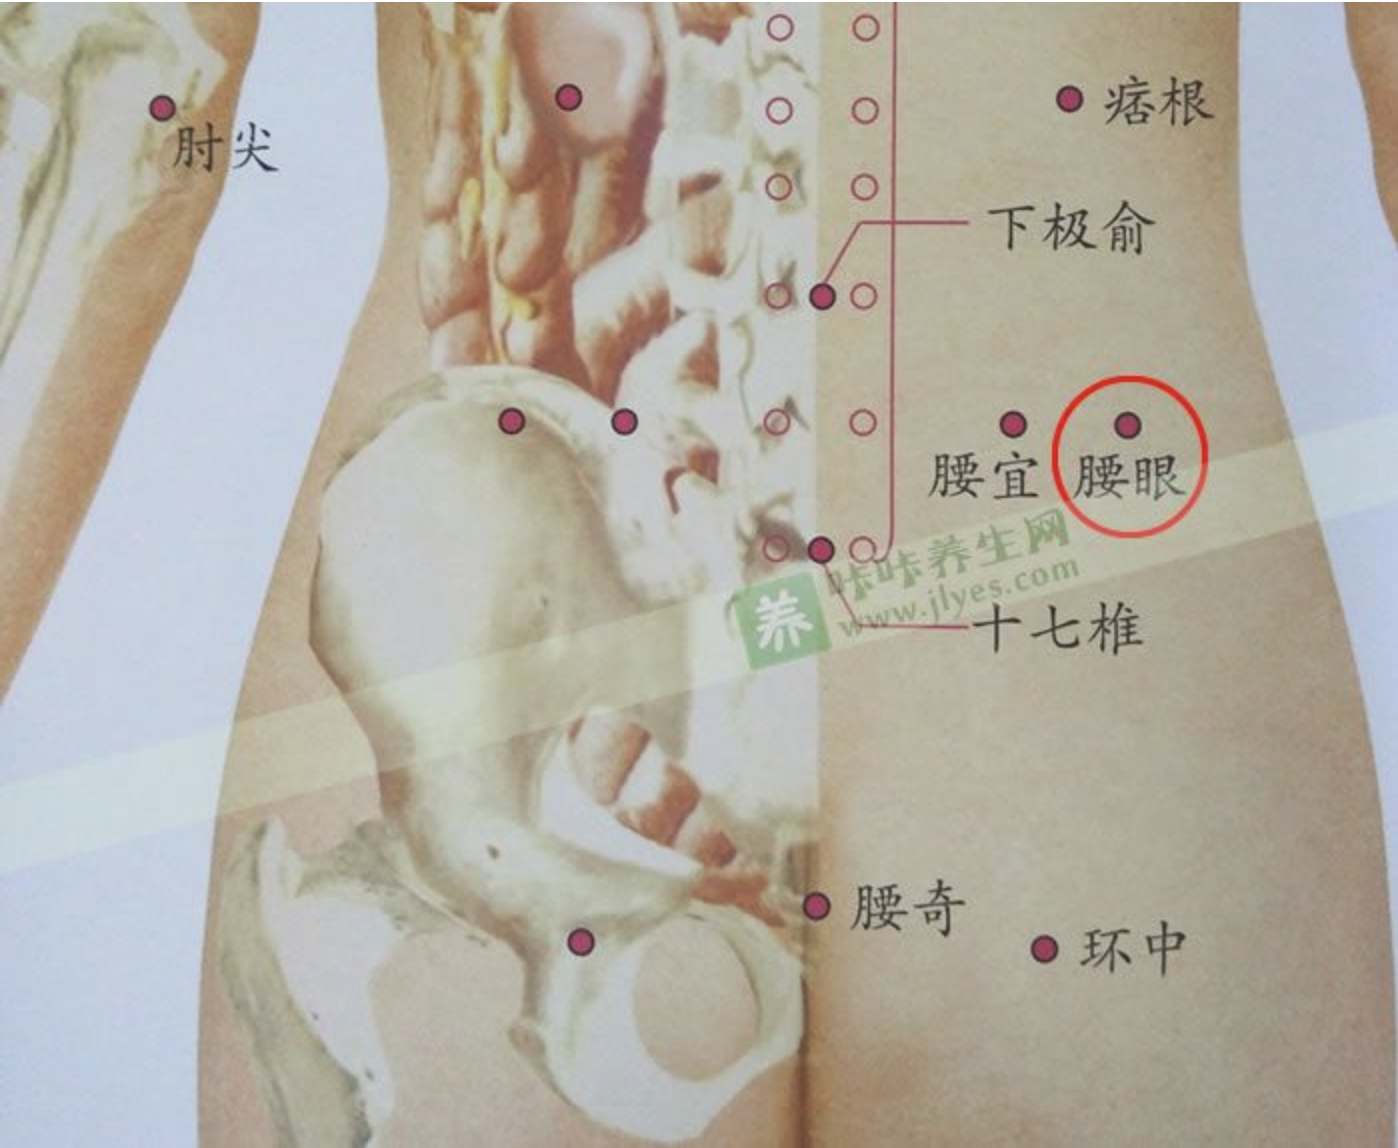

腰眼

【定位】 在腰部,当第 4 腰椎棘突下,旁开约 3.5 寸凹陷中。

【主治】 腰痛,月经不调,带下,虚劳。

【刺灸法】 直刺 1 ~ 1.5 寸;可灸。